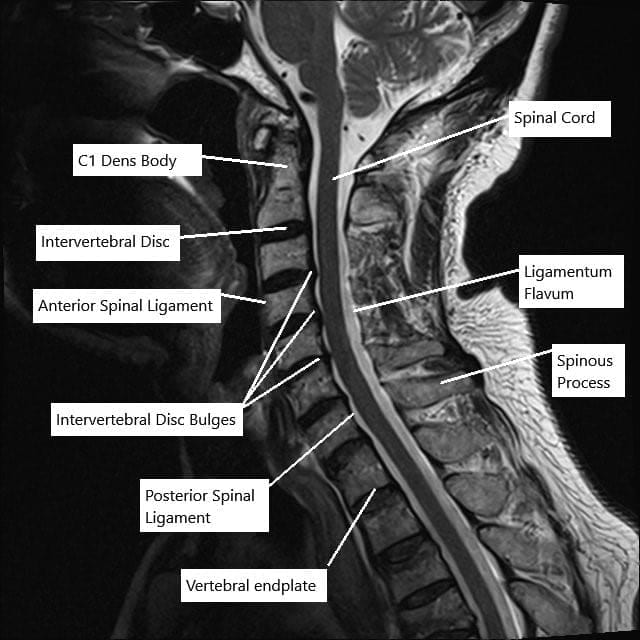

MRI of the cervical spine in sagittal section showing disc herniations.

The cervical spine consists of seven vertebrae that protect the spinal cord and allow head and neck motion. Between the vertebrae are discs that absorb shock and provide flexibility. Small openings between bones (foramina) let nerves branch from the spinal cord to the shoulders, arms, and hands.

When the canal or foramina become smaller, the spinal cord or nerves can be squeezed, leading to pain and neurological symptoms.

- MRI scans: Offer the best look at soft tissues, discs, and the spinal cord itself.

MRI findings help determine whether symptoms come from nerve or spinal cord compression and guide treatment decisions.